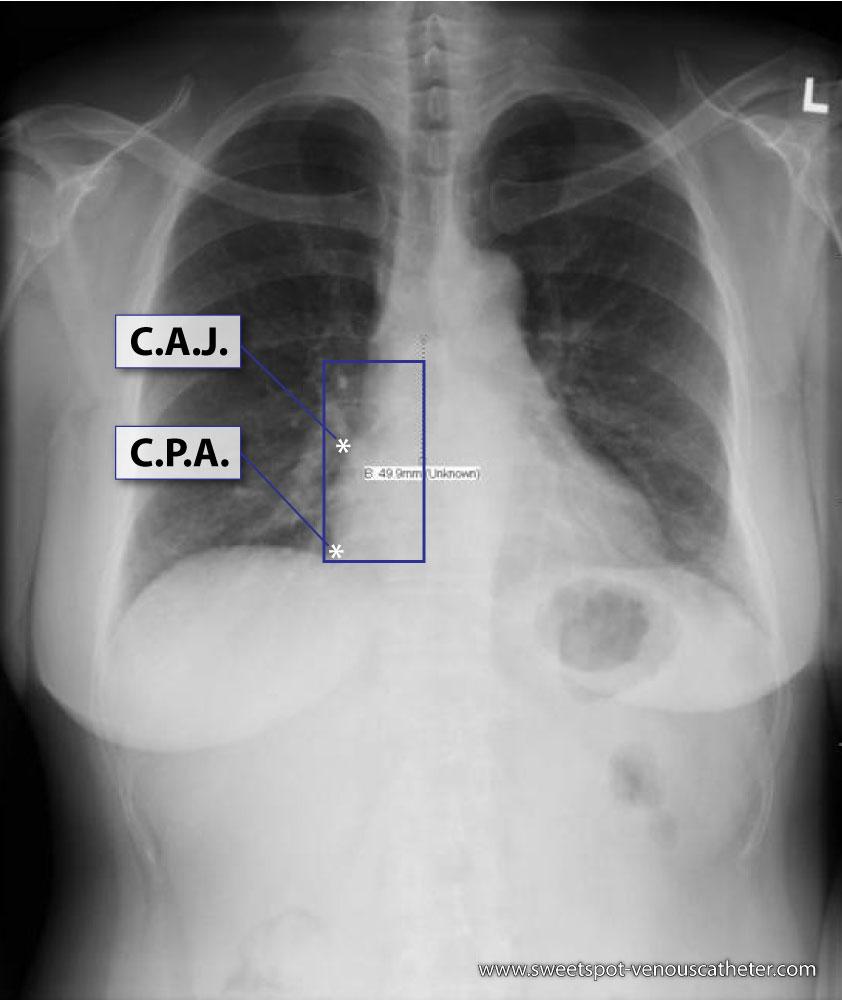

Figure - 01

CXR Sweet Spot™ Box Measurements |